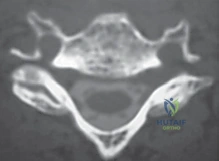

- التصوير المقطعي (CT Scan): قد يُطلب للحصول على تفاصيل أدق للتشريح العظمي.

3. النتوءات العظمية (Osteophytes/Bone Spurs)

كرد فعل طبيعي لاحتكاك العظام الناتج عن تآكل الغضاريف، يقوم الجسم بتكوين زوائد عظمية لمحاولة تثبيت المفصل. للأسف، تنمو هذه الزوائد غالباً داخل القناة الشوكية أو في مسار الأعصاب، مما يسبب ألماً شديداً.

هذه هي المرحلة الأهم والأكثر حساسية. يقوم الجراح بإزالة أي نتوءات عظمية (Osteophytes) أو أجزاء من الغضروف الممزق التي تضغط على الأعصاب الشوكية أو الحبل الشوكي، مما يعيد للقناة الشوكية اتساعها الطبيعي.